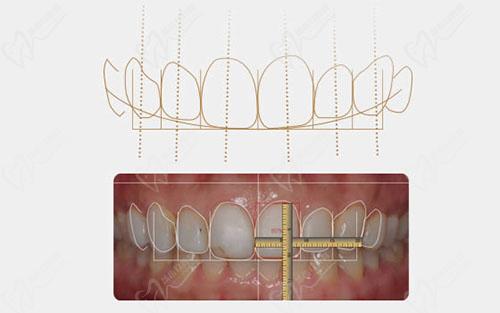

其中主推项目是四维美学正畸,是根据东方人的脸型,结合正畸美学和全数字化科技,再融入德国CT定位技术,通过CT-三维立体定位方向及角度,为患者定制专属矫正方案,重塑面部轮廓。改善牙齿外观。价格在19800元-45800元(具体以面诊为准)。